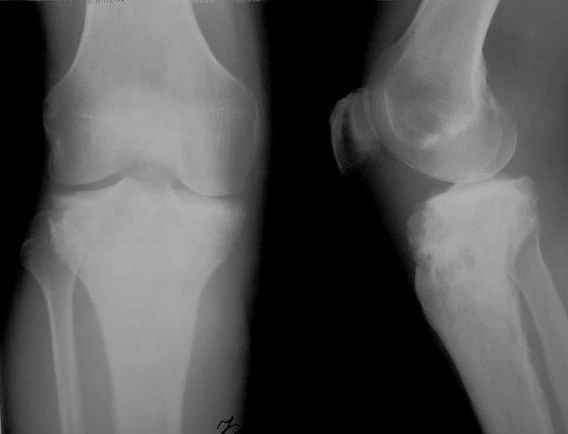

первичная костная лимфома

Всем привет! Кому интересно - может лицезреть мое личное наблюдение первичной костной лимфомы с поражением правой большеберцовой кости (см. аттач).

Пациент: мужчина, 46 лет. Анамнез прослеживается в течение 1,5 лет - начало заболевания с появления болей. С уважением, Виталий Тазалов.